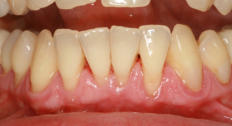

Parodontitis:

Bei der Parodontitis (Entzündung des Zahnbettes oder des Zahnhalteapparates) handelt es sich um eine chronische Erkrankung, die zum Abbau der zahntragenden Gewebe führt und mit Zahnfleischtaschen, erhöhter Lockerung des Zahnes, evtl. Schmerzen, bis zum Zahnausfall einhergeht. Parodontitis kann einzelne oder alle Zähne befallen und in seltenen Fällen schon bei Kindern und Jugendlichen auftreten. Sie verläuft lange still und unbemerkt und wirkt sich auch schädigend auf das Herz-Kreislaufsystem, Körperfunktionen und Organe aus.

Ursachen der Parodontitis:

Ursache für die Parodontitis sind bakterielle Zahnbeläge (Plaque) am Zahnfleischrand, die über lange Zeiträume bestehen und durch unzureichende Mundpflege entstehen. Die Bakterien der Plaque führen zunächst zur Entzündung des Zahnfleischsaumes (Gingivitis). Nach längerer Zeit vertieft sich die sog. Zahnfleischfurche zu einer sog. Zahnfleischtasche. In der Zahnfleischtasche können mehr und mehr Bakterien Platz finden. Schließlich greift die Entzündung auch auf die Knochenstrukturen des Zahnhalteapparates über. Damit ist eine Parodontitis entstanden, in deren Verlauf der zahntragende Knochen zerstört wird. Zusätzliche Faktoren, die das Entstehen einer Parodontitis fördern und den Verlauf verschlimmern, sind Rauchen, genetische Faktoren und bestimmte Erkrankungen des Gesamtorganismus (insbesondere Diabetes), funktionelle Überlastungen einzelner Zähne, unbehandelte Karies, Zahnengstände sowie überstehende Kronen- oder Füllungsränder, die Schlupfwinkel und damit Brutstätten für Bakterien bilden.